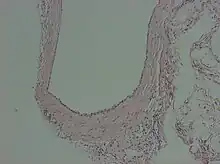

Peritoneal inclusion cyst

A peritoneal inclusion cyst is a cyst-like structure that appears in the pelvis due to non neoplastic reactive mesothelial proliferation, often as a consequence of prior episodes of pelvic inflammation, as can occur in pelvic inflammatory disease. It has the potential to mimic ovarian cysts, hydrosalpinx or even malignancy, due to its nonspecific anechoic appearance.[2]